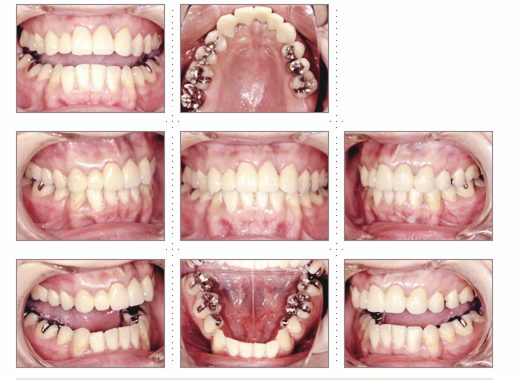

症例3

主婦 56才 女性

入れ歯が合わず食事がうまくできないので、食べれるようになりたい。人前で堂々と話をしたり、笑ったりしたい、というご希望でした。

術後は、よく噛めるようになり、栄養のバランスがよくなり、肌にツヤとハリが出て、エステに通うより効果がありました、と喜んでいただきました。